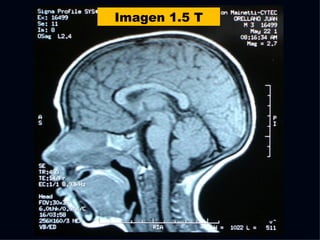

The document discusses the contributions of various figures in the field of medical imaging, including Wilhelm Röntgen and his discovery of X-rays, and the development of CT imaging and MRI technology. It highlights the historical significance of early imaging techniques and the initial skepticism from medical professionals regarding their usefulness. Key milestones in imaging are noted, along with the eventual acceptance of such technologies in clinical practice.